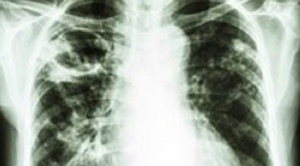

Evaluasi batuk kronis bisa menyulitkan klinisi karena ada banyak sekali kemungkinan etiologi yang mendasari, termasuk tuberkulosis paru dan asma. Secara umum, batuk...(Baca Selengkapnya)

-   Perbedaan PCR GeneXpert MTB/RIF Konvensional dan Ultra untuk Diagnosis Tuberkulosis – Artikel Terkini! Perbedaan PCR GeneXpert MTB/RIF Konvensional dan Ultra untuk Diagnosis Tuberkulosis – Artikel Terkini!Pemeriksaan PCR geneXpert MTB/RIF ultra telah dikembangkan untuk dapat lebih sensitif dan spesifik daripada geneXpert MTB/RIF konvensional, dalam mendiagnosis tuberkulosis (TB). Kedua...(Baca Selengkapnya)